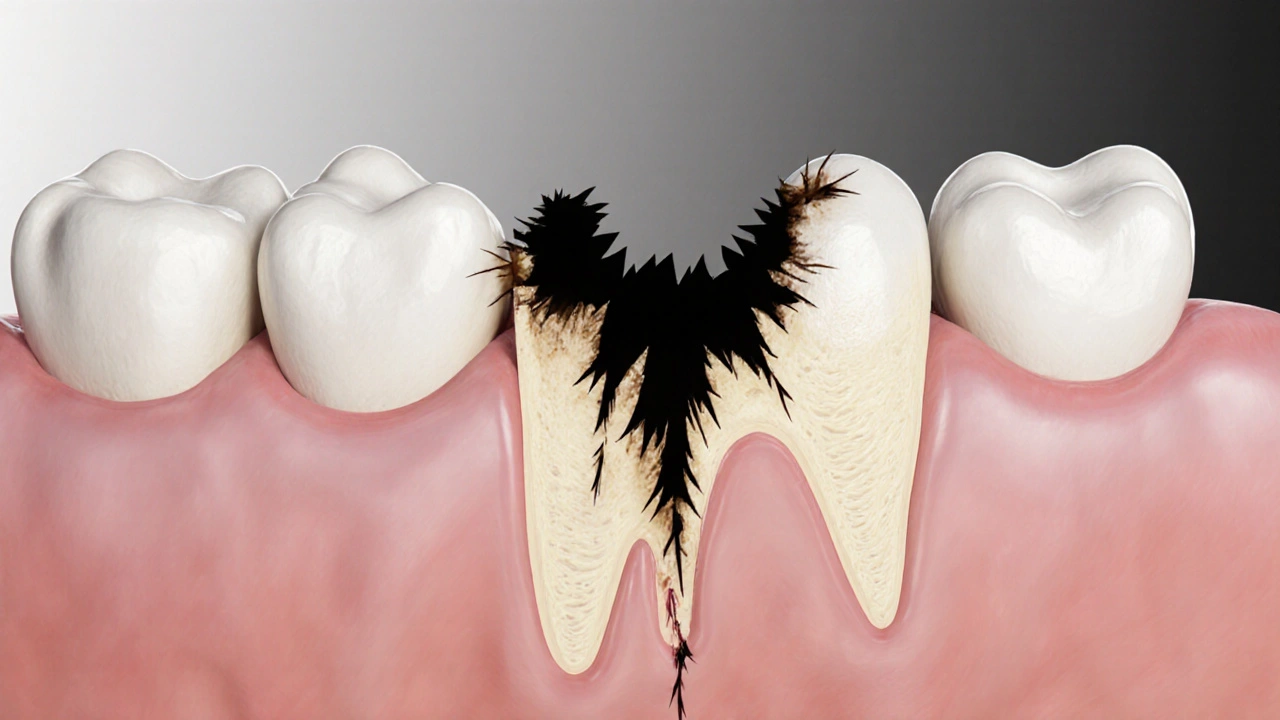

Křížový řez zubem s ukrytým poškozením, které se šíří směrem k zubní dřeni.

Co se stane, když káze necháte?

Nejprve se káze rozšíří do sousedního zubu. Pak se dostane k dásni. Pak k kosti. Pak se zub začne hýbat. Pak ho musíte vytrhnout. A pak se musíte rozhodnout, jestli chcete zubní implantát, most nebo zůstat bez něj.

Nejhorší je, že káze nezůstává jen na jednom zubu. Bakterie se šíří. A když je jeden zub ztracený, zvyšuje se zátěž na ostatní. A to znamená, že všechny ostatní zuby budou pod větším tlakem. A to znamená, že se budou poškozovat rychleji.

Nejde jen o jeden zub. Jde o celou čelist. A o vaši schopnost jíst, mluvit, se smát.